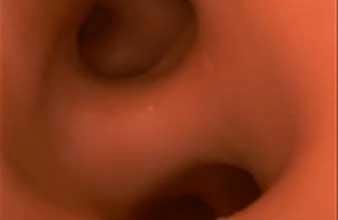

Insertion through the nose

Videos demonstrating nasal insertion of the scope.